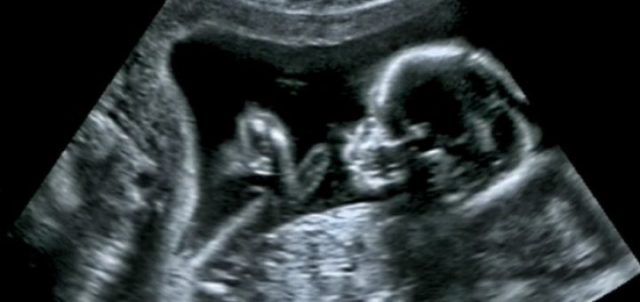

Çdo nënë e re pret me padurim për ditën kur do të shoh për herë të parë në ultratinguj fëmijën e saj. Infermierja tregon pjeset…